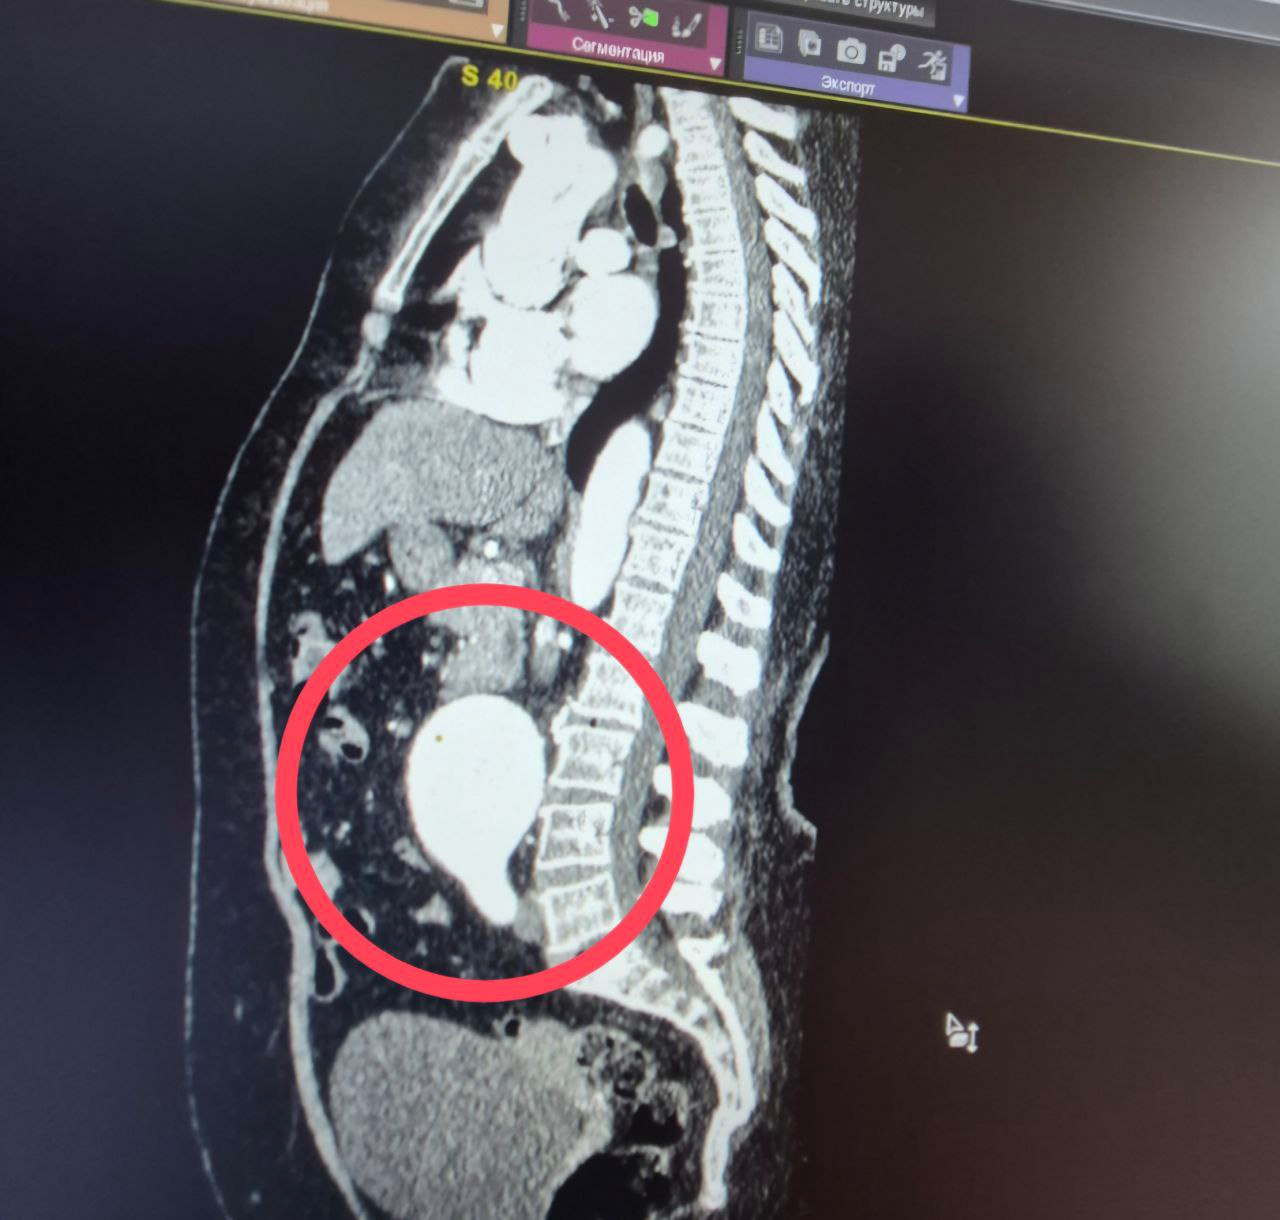

Как пояснили медики, к ним поступила 60-летняя пациентка с крайне опасным диагнозом — мешотчатая аневризма брюшной аорты.

«Это патологическое расширение главного сосуда организма, которое в любой момент может привести к внутреннему кровотечению. Случай действительно уникальный — аневризма брюшной аорты считается «бомбой замедленного действия», а мешотчатая форма особенно опасна из-за риска мгновенного разрыва.

Ситуация была настолько серьезной, что в проведении операции женщине отказали даже в областных клиниках», — пояснили в больнице.